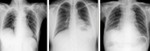

[画像診断]横隔膜挙上の鑑別診断【解答】 肝腫大、横隔神経麻痺、肺下胸水 2010-10-06